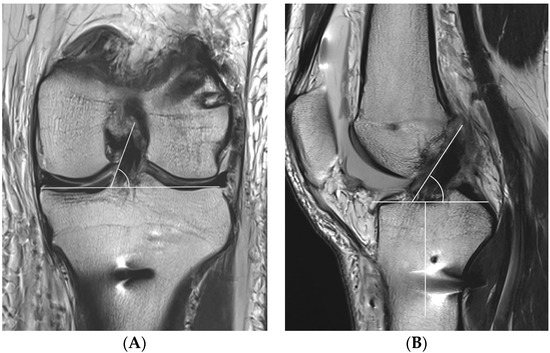

One day after ACLR, all patients underwent MRI with a 3.0-T system apparatus (Signa HD, GE Healthcare; Milwaukee, WI, USA) to evaluate for graft inclination. The graft inclination on the coronal plane was defined as the angle between the medial margin of the ACL graft through more than one slice and a line parallel to the tibial plateau at the level of the middle of the medial collateral ligament (Figure 5A). Because the entire ACL graft is unable to be visualized on one slice, if the medial margin of the ACL graft is marked and scrolled while watching the monitor, a line can be clearly drawn. The graft inclination on the sagittal plane was defined as the angle between the anterior margin of the ACL graft and a line perpendicular to the long axis of the tibia at the level of the Blumensaat line (Figure 5B).

Figure 5.

The coronal graft inclination (A) is defined as the angle between the medial margin of the anterior cruciate ligament (ACL) graft and a line parallel to the tibial plateau at the level of the middle of the medial collateral ligament. The sagittal graft inclination (B) is defined as the angle between the anterior margin of the ACL graft and a line perpendicular to the long axis of the tibia at the level of the Blumensaat line.

Regarding the femoral tunnel location, it was located at 29.7 ± 4.4% in the posterior to anterior (deep to shallow) direction and at 24.1 ± 5.9% in the proximal to distal (high to low) direction. The mean femoral graft bending angle was 113.9 ± 5.7°, and the mean femoral tunnel length was 35.2 ± 3.1 mm (Table 3). There were no cases of a femoral tunnel length <30 mm because the guide pin was redirected for those <30 mm while making the knee joint flexion to approximately 110°. Posterior wall breakage was observed in five patients (8.3%). In the MRIs, the mean coronal graft inclination was 69.2 ± 4.7°, and the mean sagittal graft inclination was 52.4 ± 4.6° (Table 3). The mean posterior tibial slope 241 was 7.9 ± 3.5, and there was no posterior tibial slope of more than 12°.

In terms of graft inclination, Jamsher et al. [31] applied and compared four drilling techniques (the transportal technique using a flexible reamer system, the transportal technique using a rigid reamer system, outside–in retrograde drilling technique, and the transtibial drilling technique) for ACLR and demonstrated that the transportal technique using a flexible reamer system and outside–in retrograde drilling technique had outcomes more similar to those of sagittal and coronal inclinations than the transportal technique using a rigid reamer system and transtibial technique. In the study, the inclinations of the native ACL in the sagittal plane and coronal plane were 49.3 ± 4.2° and 73.6 ± 3.4°, respectively, and the graft inclination in ACLR with the transportal technique using a flexible reamer system in the sagittal plane and coronal plane were 49.9 ± 5.0° and 69.3 ± 4.5°, respectively. Other studies also reported that the sagittal inclination of the native ACL was 51–52° [20,32]. Snoj et al. [21] reported 52.2 ± 4.4° for the sagittal inclination of native ACL and 65.2 ± 6.6° for coronal inclination. Thus, the sagittal and coronal inclinations in our study were as close as within a 5° difference as those from inclinations of the native ACL reported by previous studies. Because a femoral offset guide was not used when applying the flexible reamer system, we were able to easily adjust the vertical position of the femur tunnel, which seemed to affect the outcome positively [31]. Although the effect of graft inclination on the clinical outcomes of ACLR has yet to be revealed, some report that it could have effects as considerable as the femoral tunnel location. Snoj et al. [21] demonstrated that there were significant correlations between anterior tibial translation and the sagittal (p = 0.01) and coronal (p < 0.01) inclinations. Hagiwara et al. [20] reported that the lateral sagittal inclination ranged from 45.8° to 65.4° after ACLR and that a larger graft inclination was significantly correlated with graft laxity.